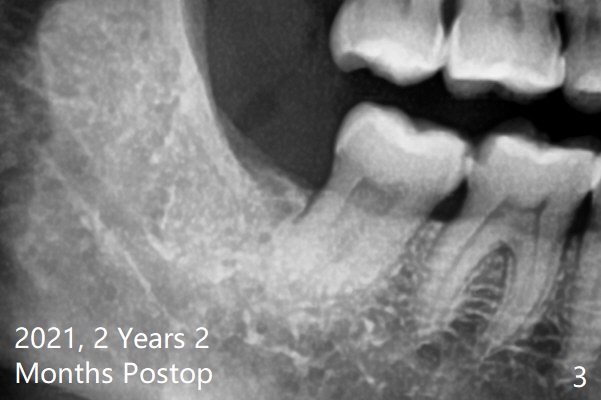

术后2年2个月#32牙槽窝密度高于#17(术后至少13年,图三)。